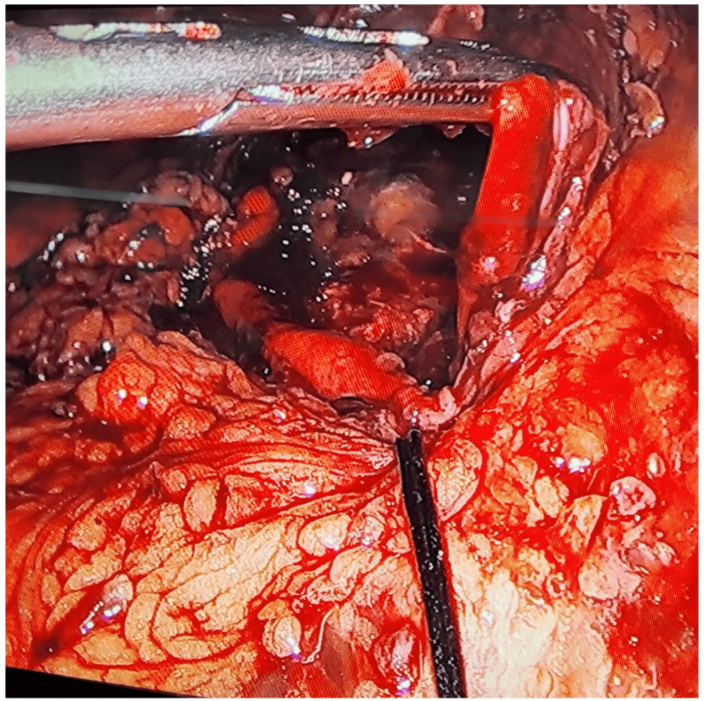

Emergency diagnostic laparoscopy revealed abundant free air in the abdominal cavity and a 3-cm perforation on the anterior surface of the stomach.

The defect was repaired laparoscopically using absorbable sutures and reinforced with an omental patch. The patient recovered without complications and was discharged on postoperative day 3 after tolerating a liquid diet.